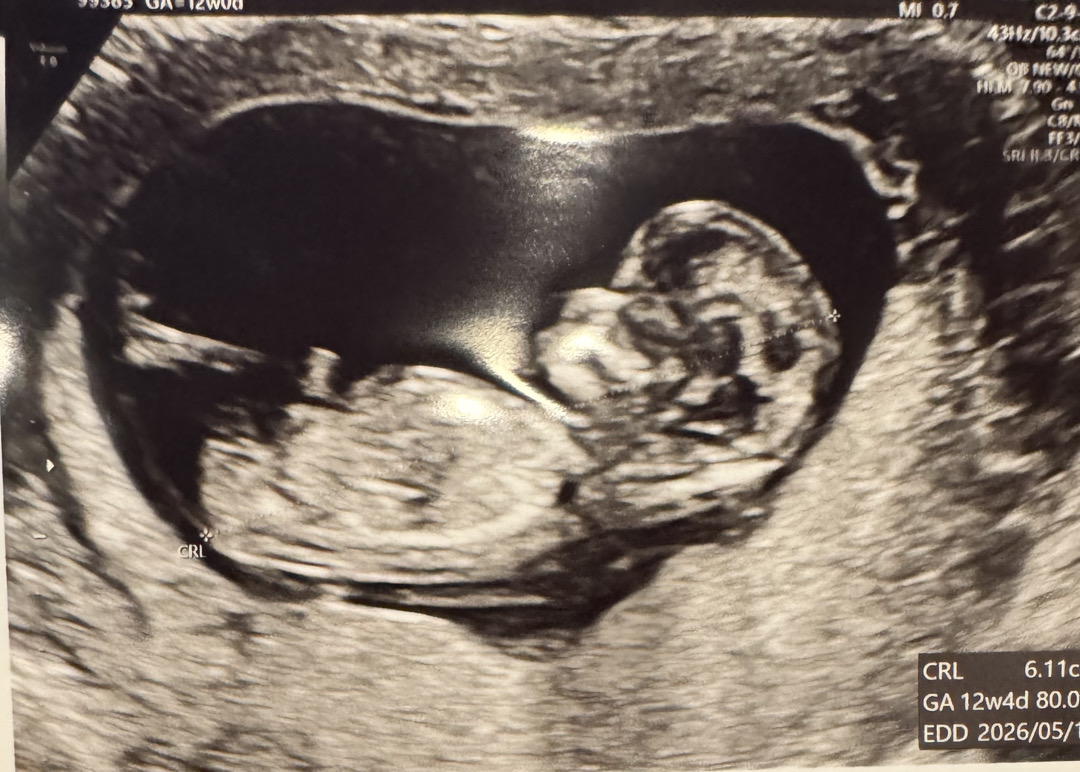

12주 각도법한번 봐주세요!!

전 아무리봐도 잘 모르겟어요…ㅠ